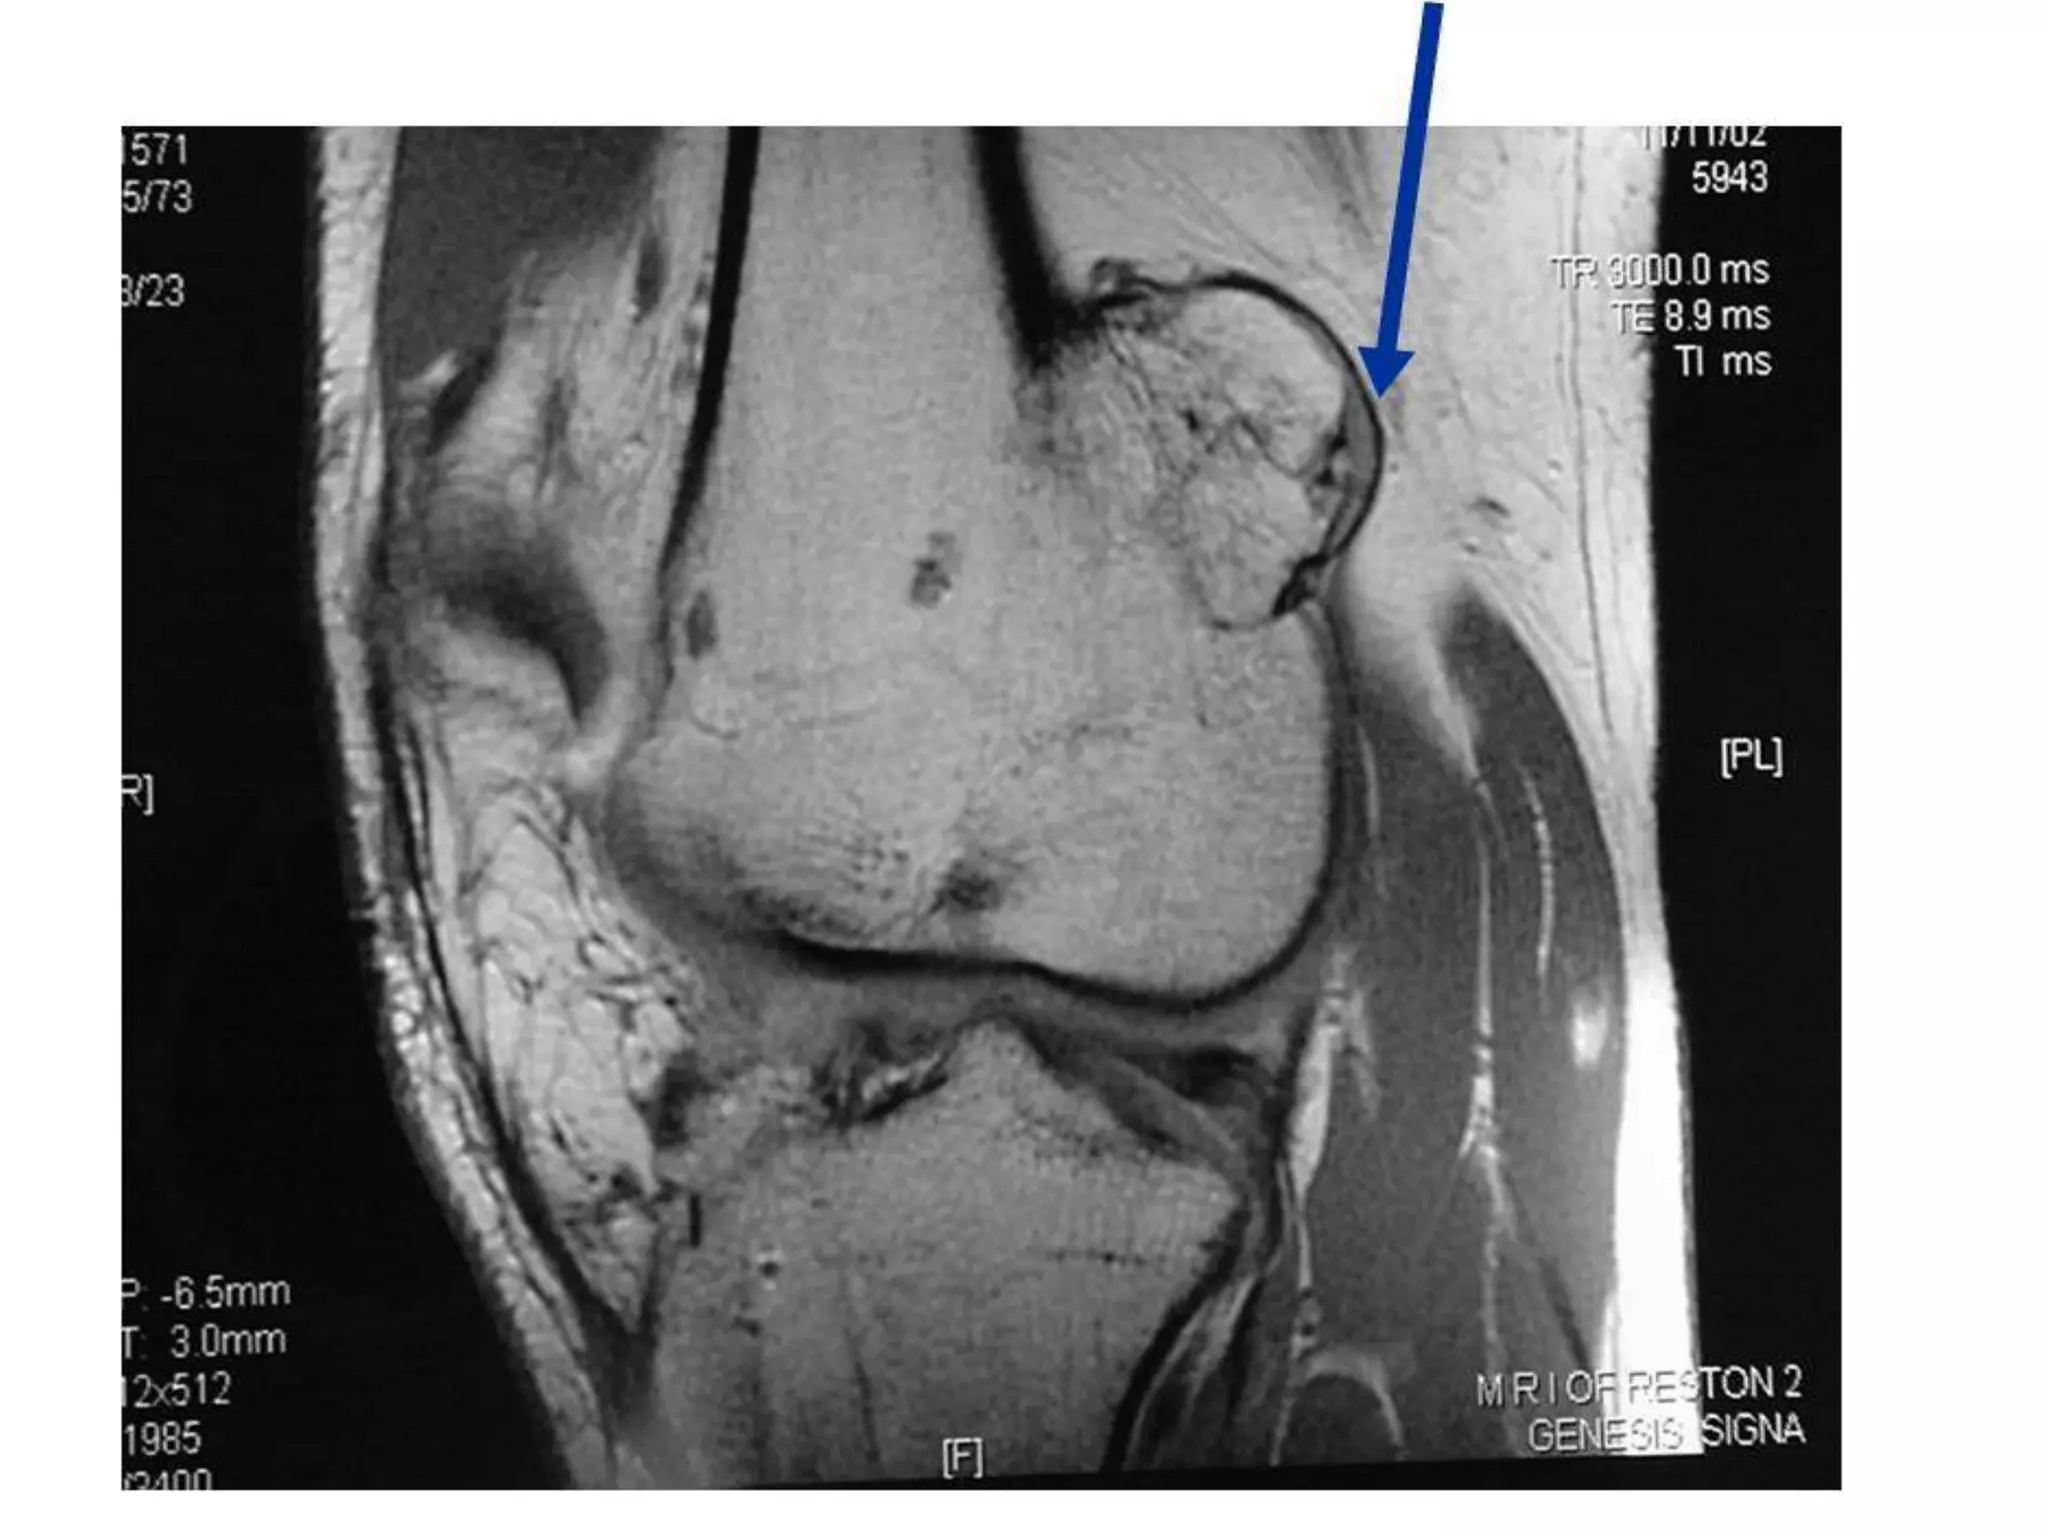

• Giant cell tumor / osteoclastoma at upper end of

left tibia

INVESTIGATIONS

• X-ray of the affected bone

A solitary radiolucent lytic lesion

Eccentrically located at the epiphyseal end of long bone

Bounded by subchondral bone plate

Centre showing soap-bubble appearance due to ridging of

the surrounding bone (homogenously lytic with trabecular

of the remnants of bone traversing it, hence giving a

loculated appearance)

Expansion or ballooning of overlying cortex

Thinning out of the overlying cortex, probably perforated at

places

No calcification within tumor, no reactive sclerosis around

the tumor and no invasion of the adjacent joint

• CT / MRI scan (detailed

staging procedure)

Reveal the extent of the

tumor, both within the

bone and beyond

Establish if the articular

surface is breached

Look for any concomitant

neurovascular structure

involvement